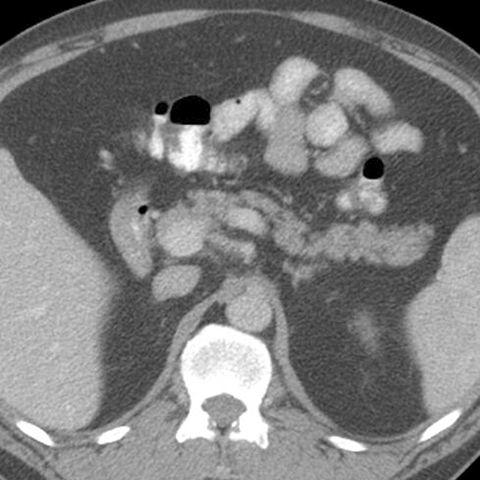

Normal Pancreas, Axial CT [2 of 5]